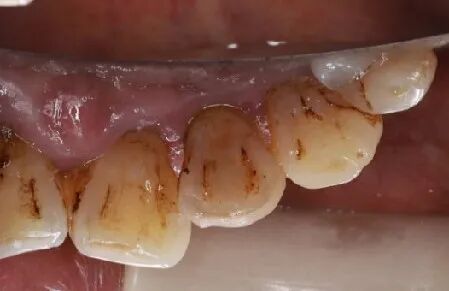

口内检查:全口牙龈轻度吸收,牙列不齐,12、22反合,口腔卫生一般。

主诉牙情况:22牙体颜色稍变暗,  松动 III 度,叩诊(-),牙 龈无红肿、溢脓、牙周袋 6mm,近远中龈乳头缺损。

术后4.5个月口内照片